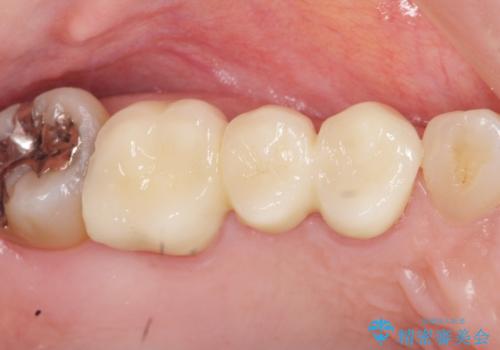

虫歯による歯の喪失 ジルコニアブリッジの製作

- 大きく歯が欠けてしまった虫歯の治療を希望され来院されました。

虫歯による歯の崩壊で歯を残すことが難しかったので抜歯を行い、インプラント・入れ歯ではなくブリッジによる咬合機能の回復を希望されました。

- 33万円(仮歯・ジルコニアクラウン×3)費用は治療当時の料金となります

ブリッジは隣の歯を削り、クラウンにしなければならないというデメリットはありますがインプラントと異なり手術をしなくてもよく、入れ歯よりも一般的にしっかりと噛むことができます。